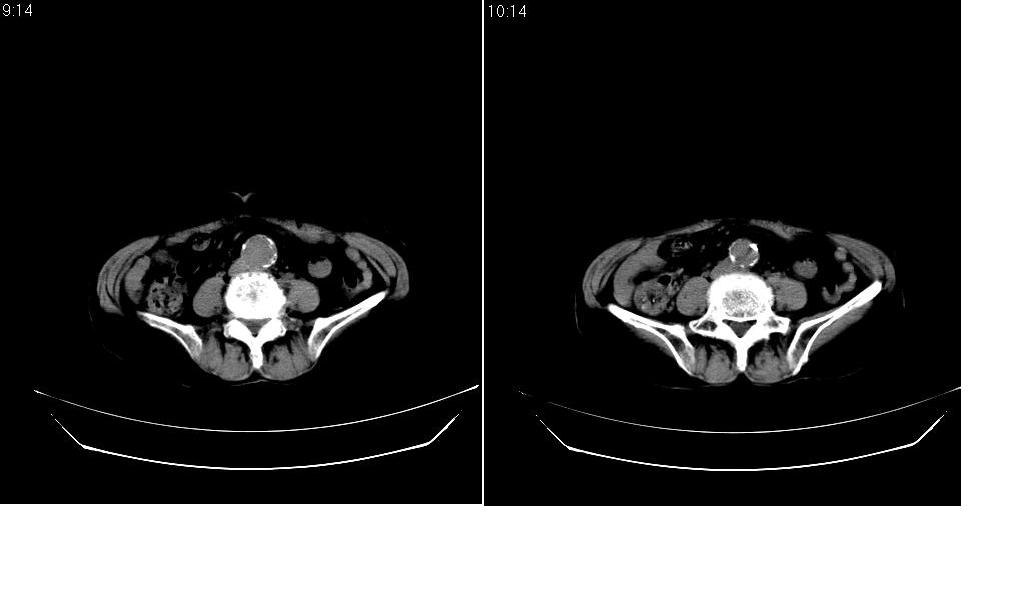

标题: CT12001:上腹部CT平扫

女73岁,病史不详,腹主动脉增宽.

考虑:腹主动脉瘤。建议增强。

腹主动脉瘤是腹主动脉壁的扩张膨出。腹主动脉瘤发生后可逐渐增大,最后破裂出血,导致病人死亡。

考虑:腹主动脉瘤。建议增强排除夹层的可能。

支持腹主动脉瘤。建议增强或mri检查。

考虑主动脉夹层,可惜没有增强,标识